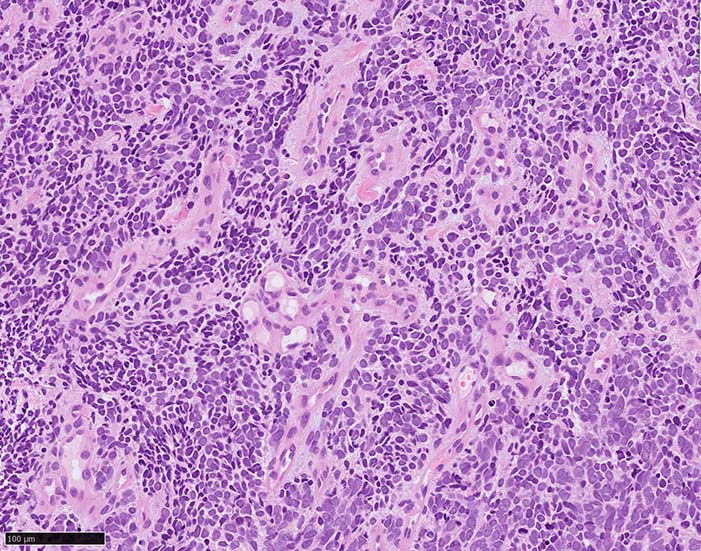

典型的な腫瘍細胞は円形, 卵円形の比較的均一な形態で「salt-and-pepper」と称される微細顆粒状クロマチンを有する小型円形核をもつ. MCPyV陽性例が均一な小型円形核を呈する傾向があり, 陰性例では, 核多形性が目立つととする報告がある.

trabecular type, intermediate type, samll cell typeの3パターンの組織型に分類されているがしばしば混在している.

- trabecular typeは円形から多稜形の腫瘍細胞が索状に配列, 3形のなかで腫瘍細胞がもっとも大きく, 円形核と比較的豊富な細胞質をもつ.

- small cell typeは濃いクロマチン, 多形性を示す核をもつN/C比大の小型腫瘍細胞がびまん性に増殖する.

- intermediate typeではtrabecular, samll cell typeの中間の腫瘍細胞サイズを示す. 組織型としてはもっとも多い.

腫瘍内浸潤リンパ球/炎症細胞は多くの症例で認められる. リンパ球の腫瘍内浸潤は予後良好因子と報告されている. 16

HE

血管を間質にしてround cellsが索状に増殖する所見. rossett様配列がある. CK20は特徴的な dot-like patternを示す. クリックで大きな画像が見られます.